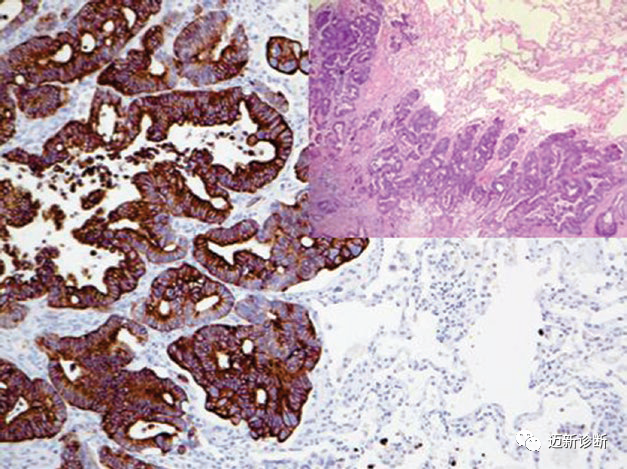

Figure 3. In Merkel cell carcinoma, CK20 shows characteristic perinuclear dot-like staining.

Figure 4. Metastatic colorectal adenocarcinoma strongly expresses CK20.